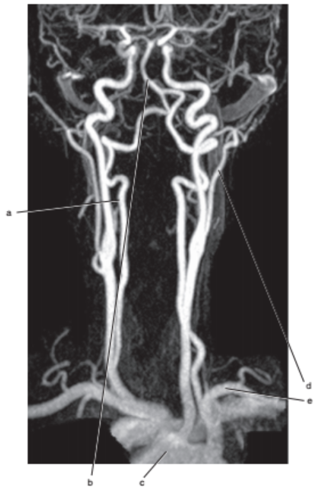

What is letter l ?

Common carotid

What is letter e ?

Subclavian artery

What is letter f ?

Common carotid artery

What is letter a ?

Vertebral artery

What is letter k ?